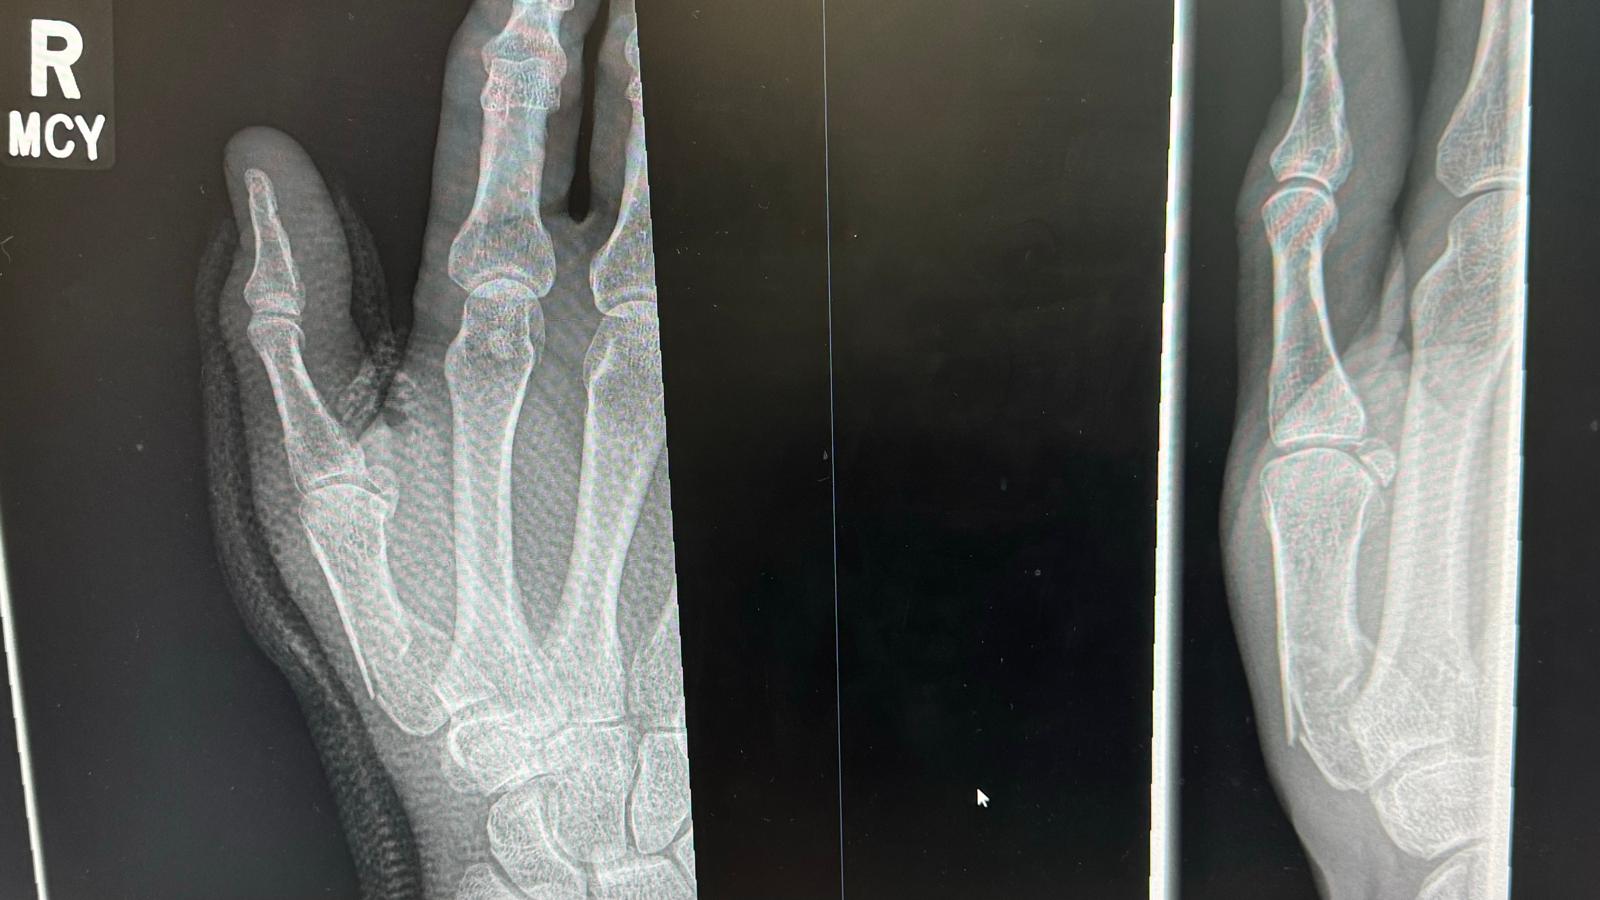

Did mine last night coming off bike hard on some acorns in the woods. Minor injury clinic was great. In Xray plaster cast and out in under an hour. Now awaiting hand-clinic appointment to see if it needs pinning (likely by all accounts).

Anyone had one of these and if so what is the likely outcome? How long out of action. It is my right hand too which is a pain and makes my job near impossible!

Cheers for all the support. Hopefully going in to get it wired together next Friday (I will believe it when I see it). Then 4 weeks till pins come ou t and another 2 weeks in plaster after that. Buggeration